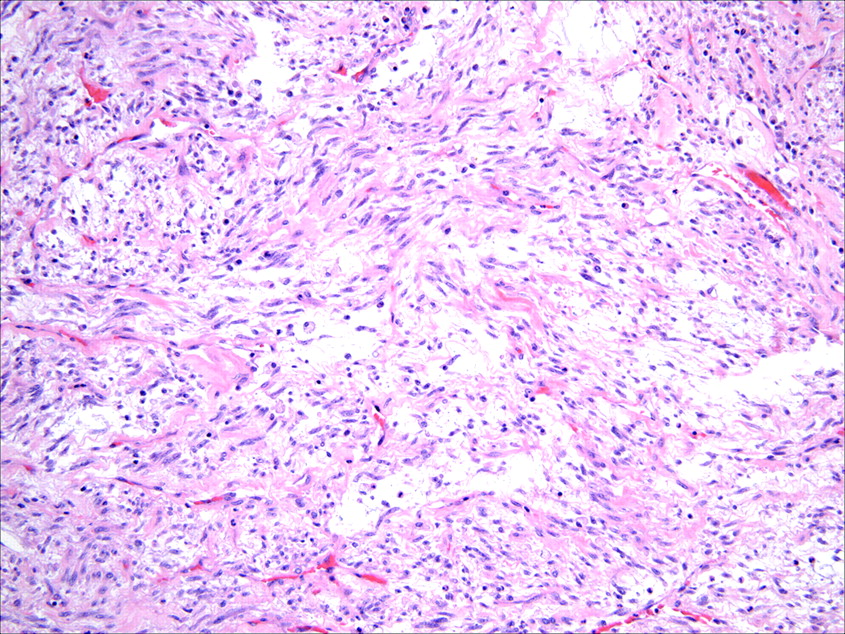

Often in children but can occur at any age. It usually occurs in children and adolescents and most commonly involves pulmonary and. Surgpath → msk → soft tissue. Inflammatory myofibroblastic tumor pathology pathology in outline format with mouse over histology previews. Inflammatory myofibroblastic tumor (imt) is a rare entity of neoplastic origin. Inflammatory myofibroblastic tumour, abbreviated imt, is an uncommon soft tissue. Inflammatory myofibroblastic tumor (imt) is an uncommon myofibroblastic neoplasm that was formerly included within the broad category of inflammatory pseudotumor. Patients usually in the pediatric age range ( am j surg pathol 2007;31:509 ) symptoms include anemia, abdominal pain, fever, weight loss and high sedimentation rate ( j. Inflammatory myofibroblastic tumor (imt), also called inflammatory pseudotumor, is a rare benign tumor composed of spindle cells with a variable infiltrate of inflammatory.

Surgpath → msk → soft tissue. Primary inflammatory myofibroblastic tumor (imt) is a very rare type of mesenchymal tumor. Inflammatory myofibroblastic tumor (imt), also called inflammatory pseudotumor, is a rare benign tumor composed of spindle cells with a variable infiltrate of inflammatory. Inflammatory myofibroblastic tumour, abbreviated imt, is an uncommon soft tissue. Caporalini c(1), moscardi s(1), tamburini a(2), pierossi n(3), di maurizio m(4),. Richard l kempson md robert v rouse md. The tumor is positive for alk (granular cytoplasmic staining), desmin (patchy) and cd10 (patchy) but negative for bcor and caldesmon.

Composed Of Spindle Cells (Key Feature) With A Variable Infiltrate Of Inflammatory Cells And Fibrous Tissue.